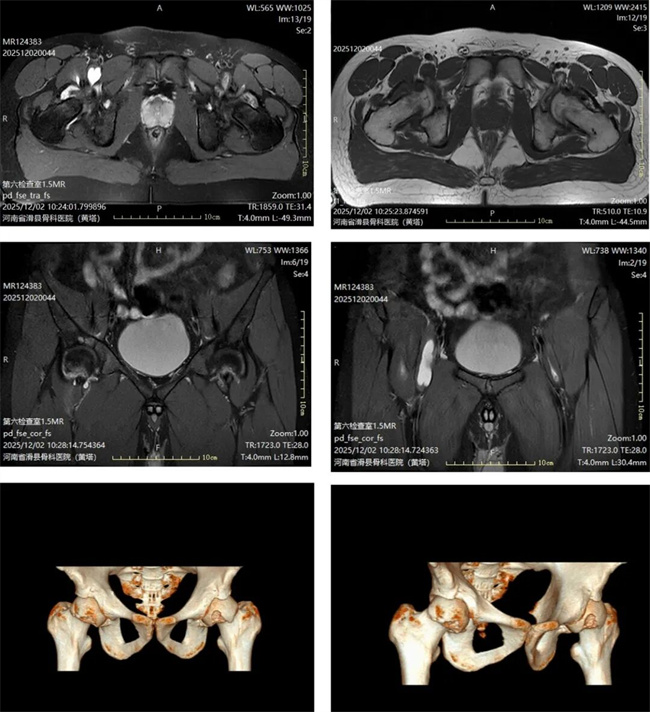

一、患者王某某,男,21岁,患者右侧髋关节疼痛一月余,查体右髋关节活动受限,压疼明显。为求进一步治疗,来到我院请专家会诊,通过各位专家会诊查体、查看影像资料并细致认真的分析后,诊断为:右髋关节滑膜疝,髂腰肌囊肿,意见:择期关节镜微创治疗。